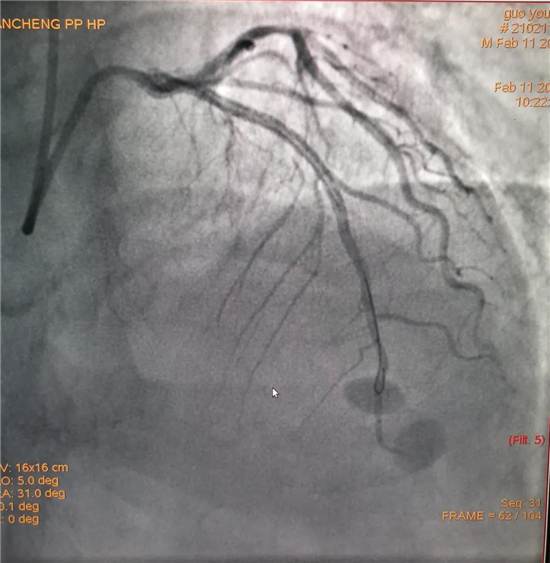

除夕,郭先生無明顯誘因突發(fā)胸痛,120急救人員到達(dá)現(xiàn)場,心電圖顯示:竇性心律完全性束支傳導(dǎo)阻滯。信息立刻發(fā)送到胸痛中心介入微信群中,心內(nèi)科值班醫(yī)生初步診斷為急性廣泛前壁心肌梗死,必須盡快進(jìn)行急診支架治療,開通血管。值班醫(yī)生電話指導(dǎo)院前治療,并立即啟動(dòng)胸痛綠色通道,24小時(shí)備班的介入治療團(tuán)隊(duì)立即到位,9:30患者被送到導(dǎo)管室行冠脈介入診療,9:40急診PCI手術(shù)隨之開始,冠脈造影檢查提示左前降支閉塞,植入支架,堵塞的血管被順利打通,患者癥狀緩解,手術(shù)非常成功,10:20患者被送往病房進(jìn)一步治療。